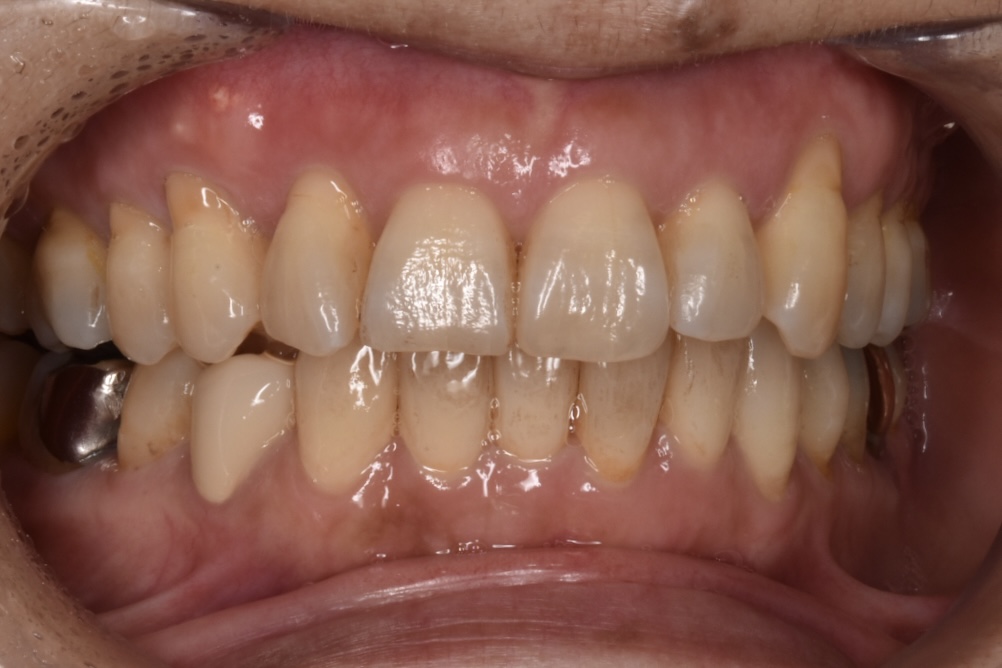

矯正前

前歯を中心に叢生(ガタガタ歯並び)がみられます。

矯正前の横顔や正面、咬合面の写真です。